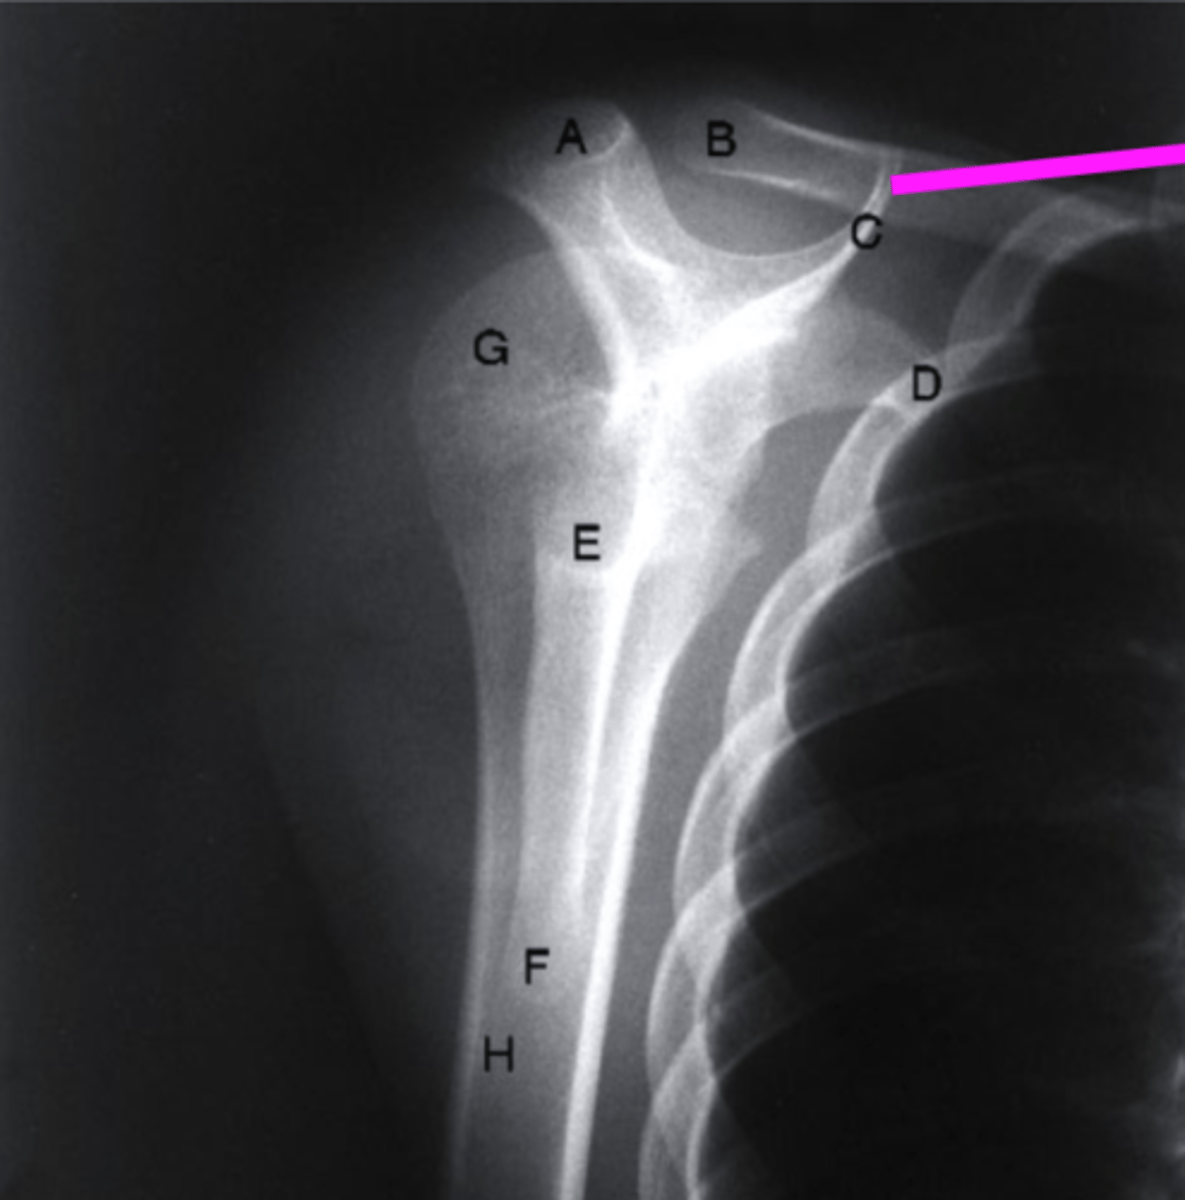

AP + IR

what view is this?

clavicle

what does the pink line point to?

spine of scapula

coracoid process

glenoid fossa of scapula

AC joint

acromion

Humeral Head

lesser tubercle